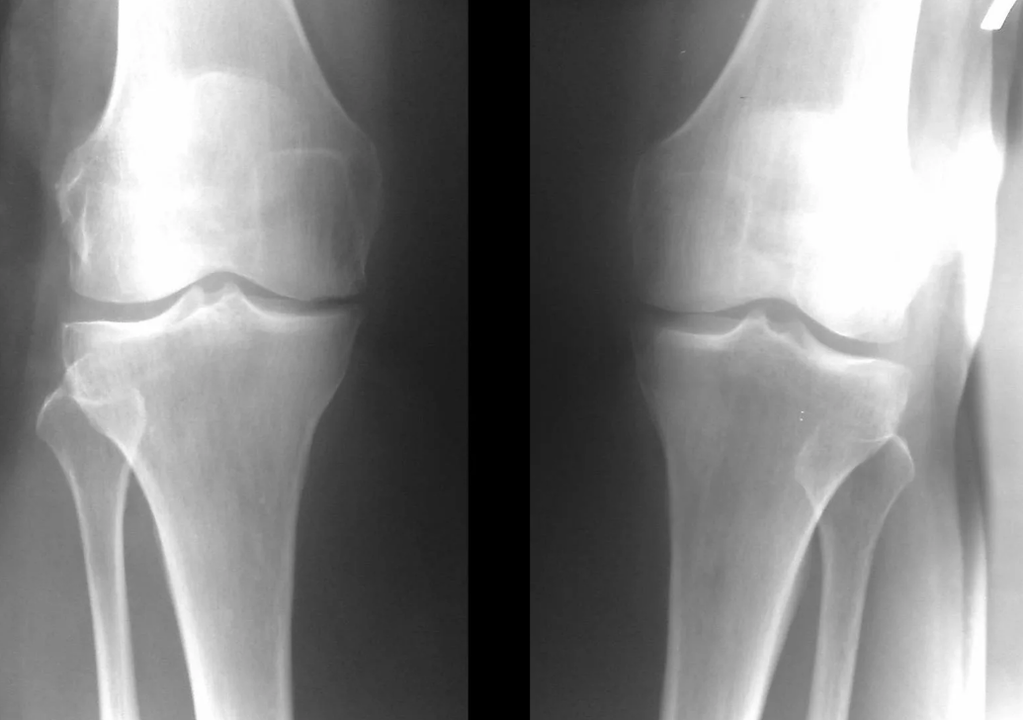

Instrumental diagnosis of osteoarthritis of the knee joint

In the vast majority of cases, an examination and an x-ray of the knee joint in two projections (direct and lateral) are sufficient.Clinical data and images help determine the stage of the disease.

In the early stages of the disease, with minor changes in bone tissue, X-ray examination is not so useful.At this stage, knee osteoarthritis can be diagnosed by arthroscopy.The precision of the method is very high;only its invasive nature and its price can stop it.

At the second stage, the cartilaginous layer becomes noticeably thinner and in some places is completely absent.Osteophytes appear along the edges of the joint surfaces.The qualitative and quantitative characteristics of the synovial fluid of the joint change: it becomes thicker, more viscous, which leads to a deterioration of its nutritional and lubricating properties.The pain is more prolonged and intense, and a crunching sound often appears when moving.There is mild or moderate restriction of movement and slight deformity of the joint.Taking painkillers helps relieve pain.

Lack of cartilage in most affected areas, severe sclerosis (hardening) of the bone, numerous osteophytes, and pronounced narrowing or absence of the joint space.The pain is almost constant, gait is impaired.Mobility is severely limited and joint deformation is noticeable.NSAIDs, physiotherapy and other standard methods of treating osteoarthritis of the knee are ineffective.